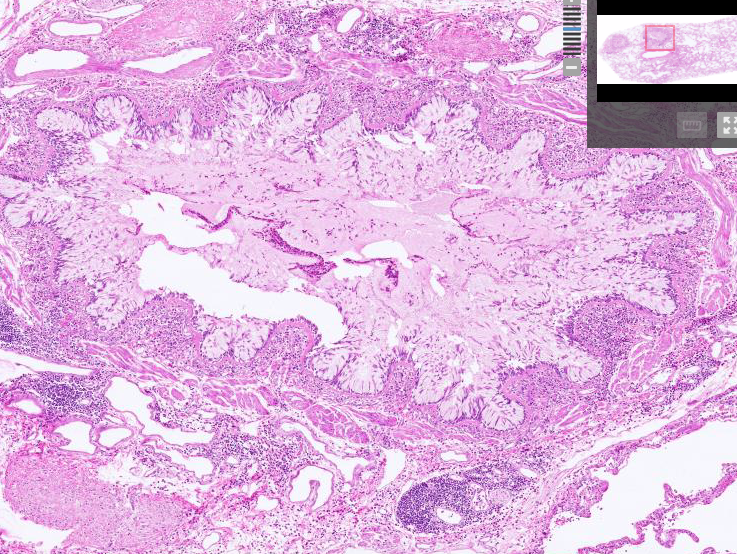

Bronchiectasis - airways filled with exudate, permanent dilation of airways,

Bronchiectasis - bronchial dilation, purulent sputum, peribronchial fibrosis